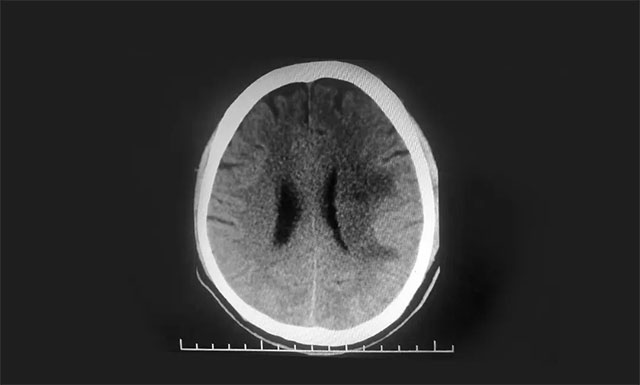

▲ 术后CT复查,出血基本已吸收

在开展严谨的评估讨论,并明确告知家属手术风险后,侯增欣主任亲自执刀,为患者开展了微创颅内血肿清除手术,通过引流管,将患者颅内的暗红色陈旧血性液体缓慢控制引出。这样,既清除了血肿,解除了对脑重要结构的压迫,又不会对周围正常脑组织造成二次损害,避免加重病情。